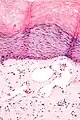

Angiokeratomas characteristically have large dilated blood vessels in the superficial dermis and hyperkeratosis (overlying the dilated vessels).

Scrotal angiokeratoma; visible large dilated blood vessels and hyperkeratosis -